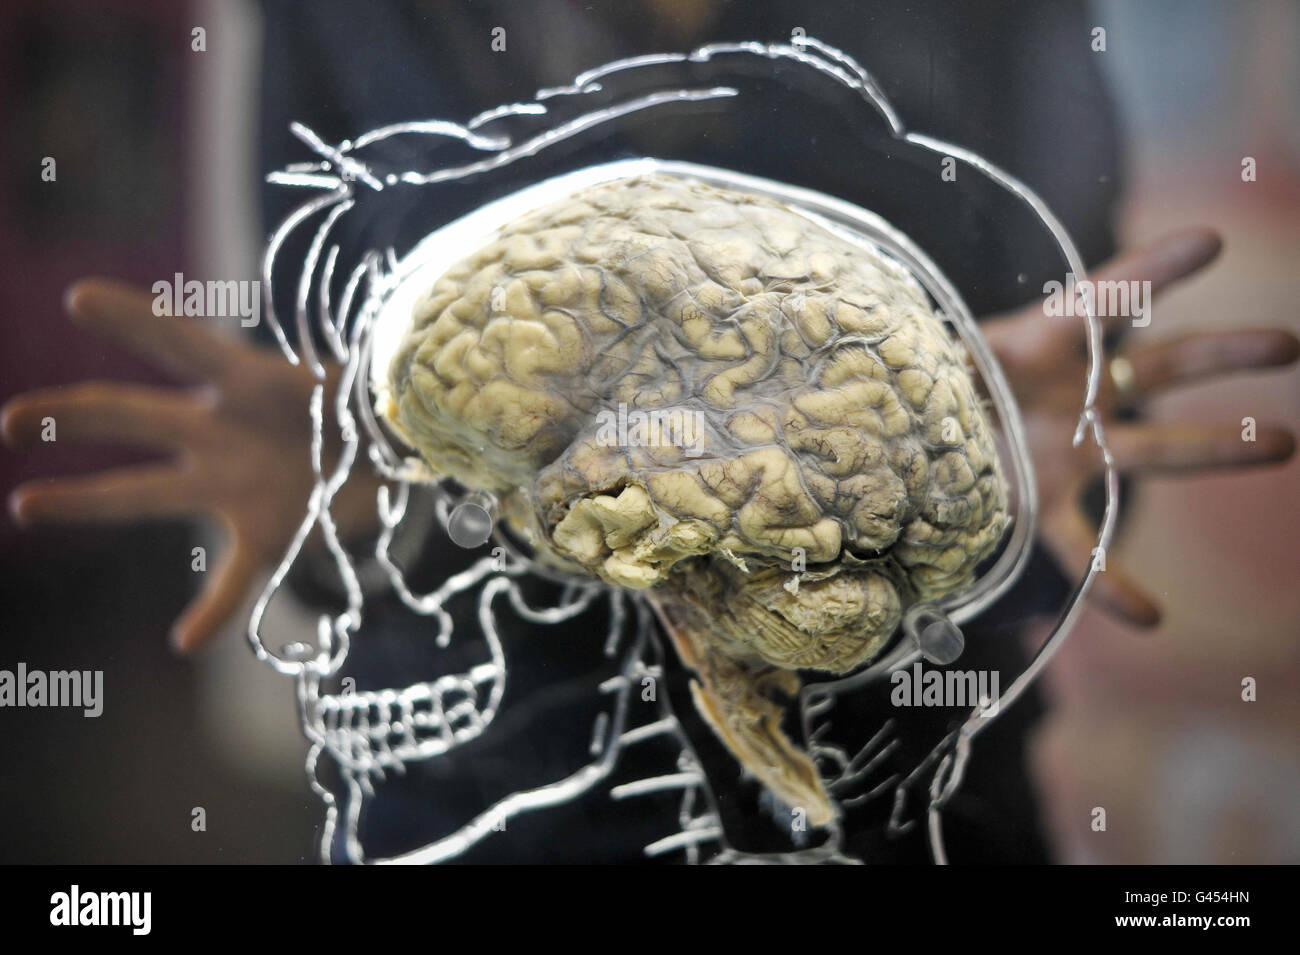

Ein echtes menschliches Gehirn in Flüssigkeit mit einem maßstabsgefertigten Skelett, zentralem Nervensystem und menschlicher Silhouette in Acryl gehauen, in der @Bristol Science Attraction als Teil der neuen Ausstellung "All About US", die am Freitag, 11. März, für die Öffentlichkeit geöffnet wird. Stockfotohttps://www.alamy.de/image-license-details/?v=1https://www.alamy.de/stockfoto-ein-echtes-menschliches-gehirn-in-flussigkeit-mit-einem-massstabsgefertigten-skelett-zentralem-nervensystem-und-menschlicher-silhouette-in-acryl-gehauen-in-der-@bristol-science-attraction-als-teil-der-neuen-ausstellung-all-about-us-die-am-freitag-11-marz-fur-die-offentlichkeit-geoffnet-wird-105834225.html

Ein echtes menschliches Gehirn in Flüssigkeit mit einem maßstabsgefertigten Skelett, zentralem Nervensystem und menschlicher Silhouette in Acryl gehauen, in der @Bristol Science Attraction als Teil der neuen Ausstellung "All About US", die am Freitag, 11. März, für die Öffentlichkeit geöffnet wird. Stockfotohttps://www.alamy.de/image-license-details/?v=1https://www.alamy.de/stockfoto-ein-echtes-menschliches-gehirn-in-flussigkeit-mit-einem-massstabsgefertigten-skelett-zentralem-nervensystem-und-menschlicher-silhouette-in-acryl-gehauen-in-der-@bristol-science-attraction-als-teil-der-neuen-ausstellung-all-about-us-die-am-freitag-11-marz-fur-die-offentlichkeit-geoffnet-wird-105834225.htmlRMG454HN–Ein echtes menschliches Gehirn in Flüssigkeit mit einem maßstabsgefertigten Skelett, zentralem Nervensystem und menschlicher Silhouette in Acryl gehauen, in der @Bristol Science Attraction als Teil der neuen Ausstellung "All About US", die am Freitag, 11. März, für die Öffentlichkeit geöffnet wird.

Ein echtes menschliches Gehirn in Flüssigkeit mit einem maßstabsgefertigten Skelett, zentralem Nervensystem und menschlicher Silhouette in Acryl gehauen, in der @Bristol Science Attraction als Teil der neuen Ausstellung "All About US", die am Freitag, 11. März, für die Öffentlichkeit geöffnet wird. Stockfotohttps://www.alamy.de/image-license-details/?v=1https://www.alamy.de/stockfoto-ein-echtes-menschliches-gehirn-in-flussigkeit-mit-einem-massstabsgefertigten-skelett-zentralem-nervensystem-und-menschlicher-silhouette-in-acryl-gehauen-in-der-@bristol-science-attraction-als-teil-der-neuen-ausstellung-all-about-us-die-am-freitag-11-marz-fur-die-offentlichkeit-geoffnet-wird-105834446.html

Ein echtes menschliches Gehirn in Flüssigkeit mit einem maßstabsgefertigten Skelett, zentralem Nervensystem und menschlicher Silhouette in Acryl gehauen, in der @Bristol Science Attraction als Teil der neuen Ausstellung "All About US", die am Freitag, 11. März, für die Öffentlichkeit geöffnet wird. Stockfotohttps://www.alamy.de/image-license-details/?v=1https://www.alamy.de/stockfoto-ein-echtes-menschliches-gehirn-in-flussigkeit-mit-einem-massstabsgefertigten-skelett-zentralem-nervensystem-und-menschlicher-silhouette-in-acryl-gehauen-in-der-@bristol-science-attraction-als-teil-der-neuen-ausstellung-all-about-us-die-am-freitag-11-marz-fur-die-offentlichkeit-geoffnet-wird-105834446.htmlRMG454WJ–Ein echtes menschliches Gehirn in Flüssigkeit mit einem maßstabsgefertigten Skelett, zentralem Nervensystem und menschlicher Silhouette in Acryl gehauen, in der @Bristol Science Attraction als Teil der neuen Ausstellung "All About US", die am Freitag, 11. März, für die Öffentlichkeit geöffnet wird.